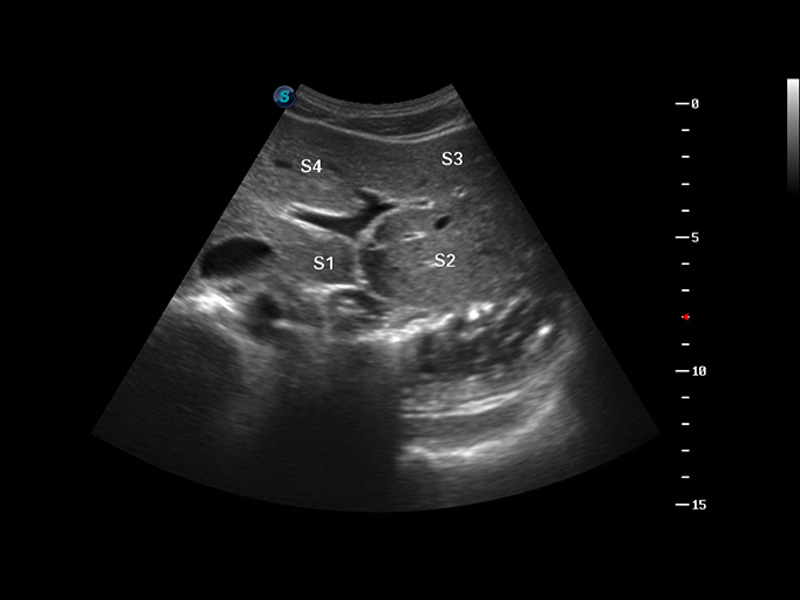

S8 EXP便携式彩色多普勒超声诊断仪是美狮贵宾会官网研发的高端全身应用型便携彩超。高通道的VIS平台融合可视化(Visual)、智能化(Intelligent)和人性化(Smart)的特点,配以美狮贵宾会官网自主研发生产的探头大家族,使您能够快速、准确的获得病人信息,提高工作效率的同时减轻疲劳。

μ-Scan微米成像